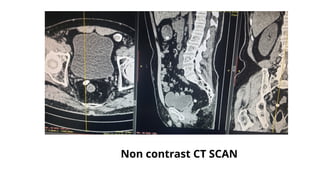

Non contrast CT SCAN